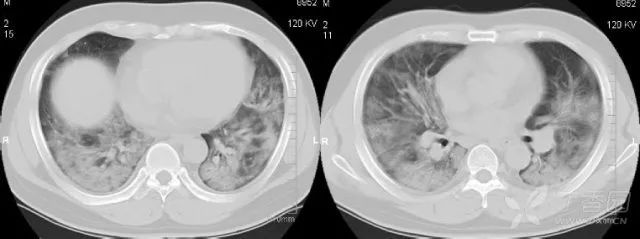

体检发现肺部结节的人越来越多,胸部ct和胸部x线有什么区别?

ct的检查原理是x光会分层穿过人体,之后通过电脑计算后二次成像

3例患者的胸部x光和胸部ct

一文掌握 6 种胸部 ct 常见征象